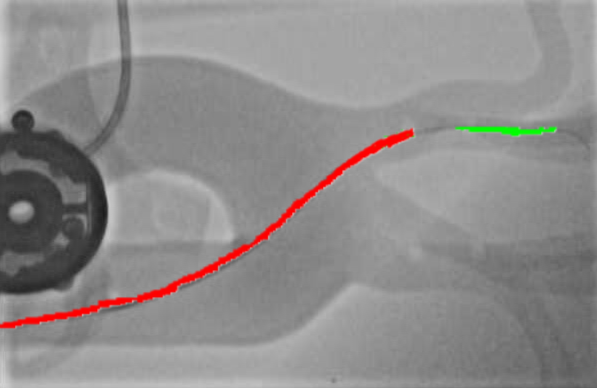

Qualitative Results. Fig. 5 illustrates the catheter and guidewire segmentation results of fine-tuning ViT on our method and different foundation models. The visualization portrays that our method excels in accurately delineating the catheter and guidewire structures, showcasing superior segmentation performance compared to other approaches. This figure further confirms that we can successfully train a federated endovascular foundation model without collecting users’ data and the trained foundation model is useful for the downstream segmentation task.

|

Animal |

Phantom |

Simulation |

Input

Ground Truth

LVM-Med

SAM

CLIP

Ours